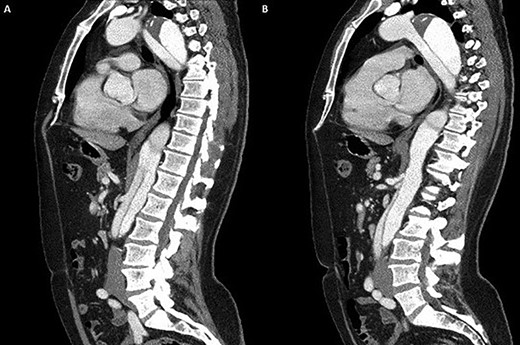

Coronal section CT scan images demonstrating the newly arranged epiaortic reconfiguration on left (A) and on the right (B) the deployed FET and antegrade flow in the descending thoracic aorta through the true lumen.

Cardiopulmonary bypass support was established using right atrial drainage and right axillary artery return. During cooling to 18°C, the aorta and epiaortic arch vessels were mobilized and encircled with tapes. At 21°C, the heart was fibrillated, aortic cross-clamp applied and antegrade cold blood intermittent cardioplegia administered to arrest the heart. At 18°C, neuroprotective protocol (topical ice to the head, intravenous steroids and mannitol administration with near infrared spectroscopy monitoring of cerebral saturations) was instituted and circulatory arrest commenced. The ascending aorta was transected 1 cm proximal to innominate artery and aortic arch inspected. Selective antegade cerebral perfusion was commenced. The aortic arch was divided in Zone 2 in order to protect the recurrent laryngeal nerve. The origin of the aberrant left vertebral artery and left subclavian artery were oversewn with a running 4/0 prolene suture. A 30/32/150 mm Thoraflex stent graft was deployed into the true lumen of the descending aorta. The cuff on the stent graft was anastomosed to the distal arch. Attention was then directed to the left common carotid and innominate arteries that were fashioned and anastomosed to the corresponding grafts on the stent graft. The aortic cross clamp was applied on the ascending aorta portion of the stent graft and total body circulation and rewarming was reinstituted. The ascending aorta was anastomosed to the stent graft 1 cm proximal to the innominate artery. A thorough de-airing drill was undertaken, the aortic cross clamp released and heart perfused. The graft on stent graft corresponding to the left subclavian artery was anastomosed and the origin on the aortic arch was oversewn. A 6-mm Dacron graft was then anastomosed to the transected left vertebral artery and origin on the aortic arch oversewn. The 6-mm Dacron graft was then anastomosed to the 8-mm side arm on stent graft corresponding to the perfusion arm. When fully rewarmed, cardiopulmonary bypass support was successfully weaned off and patient was in sinus rhythm requiring no inotropic support. Postoperatively, the patient made an uneventful recovery and was subsequently discharged home without complications and seen in the outpatient clinic as part of their routine surveillance. Computed tomography (CT) imaging performed as an outpatient demonstrated normal graft appearances, aortic arch and epiaortic vessel configurations (Fig. 3).